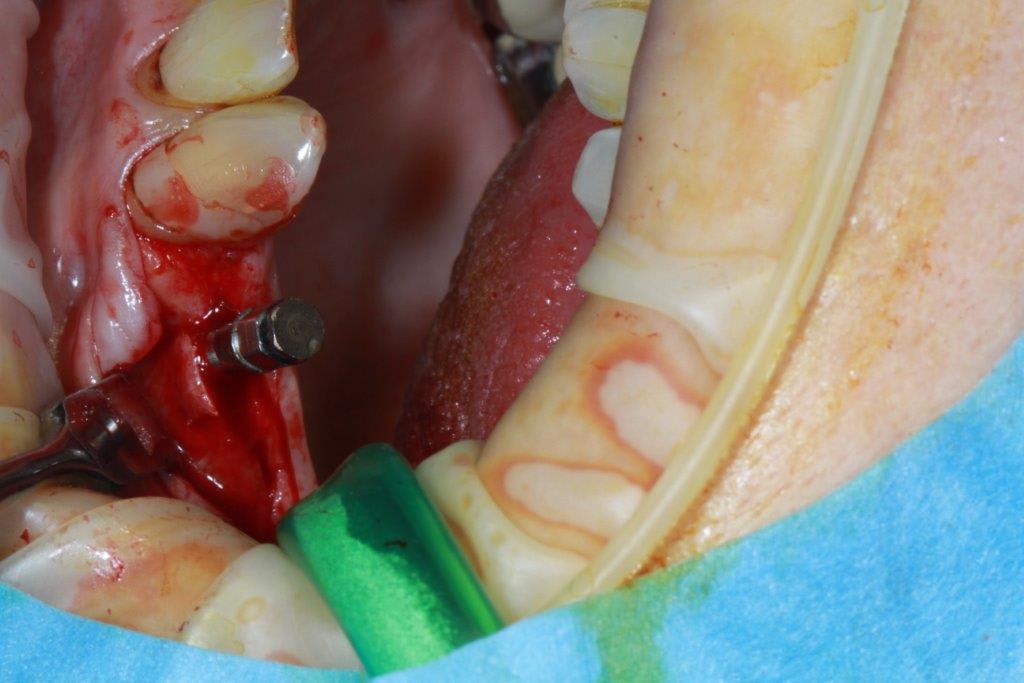

un petit cas pour ressortir ce post...et parce que c'est quand même chaud

incision crestale lame n°15, tatum, spreader Meissinger implants, PX34120 et OP34100 (summer avec eponges)

pfffff expansion/Summer.... chaud

Ce qui me la coupe c'est que tu fais ça avec une incision vraiment minimale ( tu travailles au toucher ? :) ) .

Tes patients ont de la chance.

oui, tout en sensations, et après avoir bien réfléchis sur le scan; c'est tout le principe de la manipulation osseuse, procédé qui semble voué à la disparition, avec les guides et les système GPSoguidés...en tout cas pour le moment, je prends mon pied à bricoler...

par contre je fais pas mal de radios, exemple spreaders trop près de la racine donc changement d'axe (d'où l’intérêt de l'expansion)